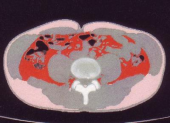

図1は、以前に載せたおなかのCT画像(ダイエット後)、

図2は、腹囲と内臓脂肪レベルのグラフです。

私の場合は、腹囲90cmの時が内臓脂肪100cm^2に相当しているようで、女性の基準に当てはまります。(^^)

皮下脂肪、特に背中やわき腹の贅肉が結構あったようです。